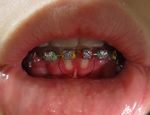

| Herpetic gingivostomatitis | Herpetic gingivostomatitis is often the initial presentation during the first herpes infection. It is of greater severity than herpes labialis which is often the subsequent presentations. Around 90% of the U.S. population is affected with this disease.[1] | |

| Herpes labialis | Infection occurs when the virus comes into contact with oral mucosa or abraded skin. | |